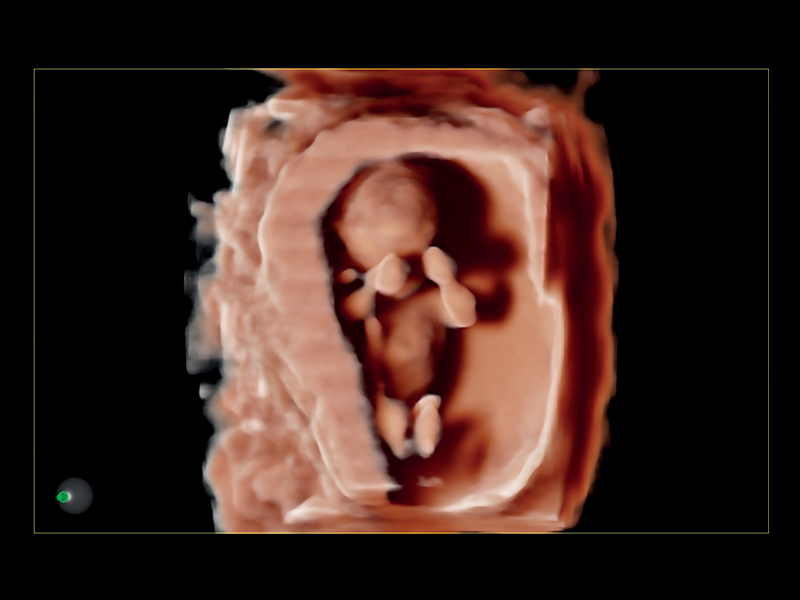

Realistic 3D/4D Depiction of the Fetus

Esaote attaches great value to the quality of its 3D/4D imaging in order to provide very detailed picture of the baby’s features, depending on the stage of fetal development. Its environment is provided by different modalities, based on how the volume can be processed and rendered.

Esaote XLight technology, with its realistic diffusion effects and shadows, emphasizes the anatomical details of the fetus in baby face scanning; XGlass creates a transparency effect; bone rendering is ideal to study the baby’s spine; TSI (Thick Slice Imaging) is suitable for well-defined and confined structures, such as the corpus callosum; finally, XSTIC accurately evaluates the fetal heart.

Clinical Images